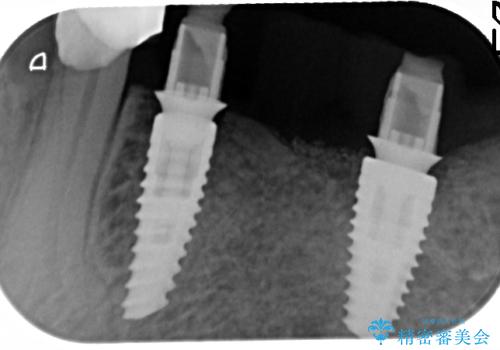

歯を失い噛めない、インプラントによる咬合機能回復

- 歯を失い噛むことができないことを悲観され来院されました。

他院で作製した入れ歯も嘔吐反射により気持ち悪くてはめていることができず、残存した右側の歯の負担は甚大です。

咬合機能を回復し、満足して食事を行えるようインプラント治療を計画します。

- 80万円(インプラント×2・アバットメント×2・ジルコニアクラウン×3)費用は治療当時の料金となります